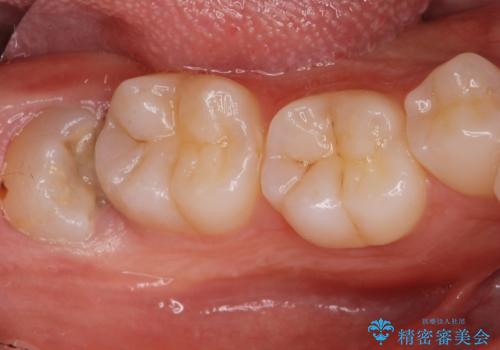

舌小帯を切りたい。

- 20代男性